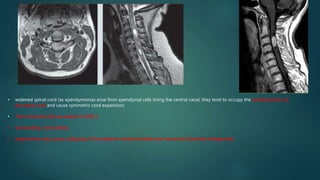

1- Nonacute Expansile neoplastic Myelopathy

• widened spinal cord (as ependymomas arise from ependymal cells lining the central canal, they tend to occupy the central portion of

the spinal cord and cause symmetric cord expansion)

• Non-tumoral cysts are present in 62% 5

• Surrounding cord odema

• large lesions may cause scalloping of the posterior vertebral bodies and neural exit foraminal enlargement